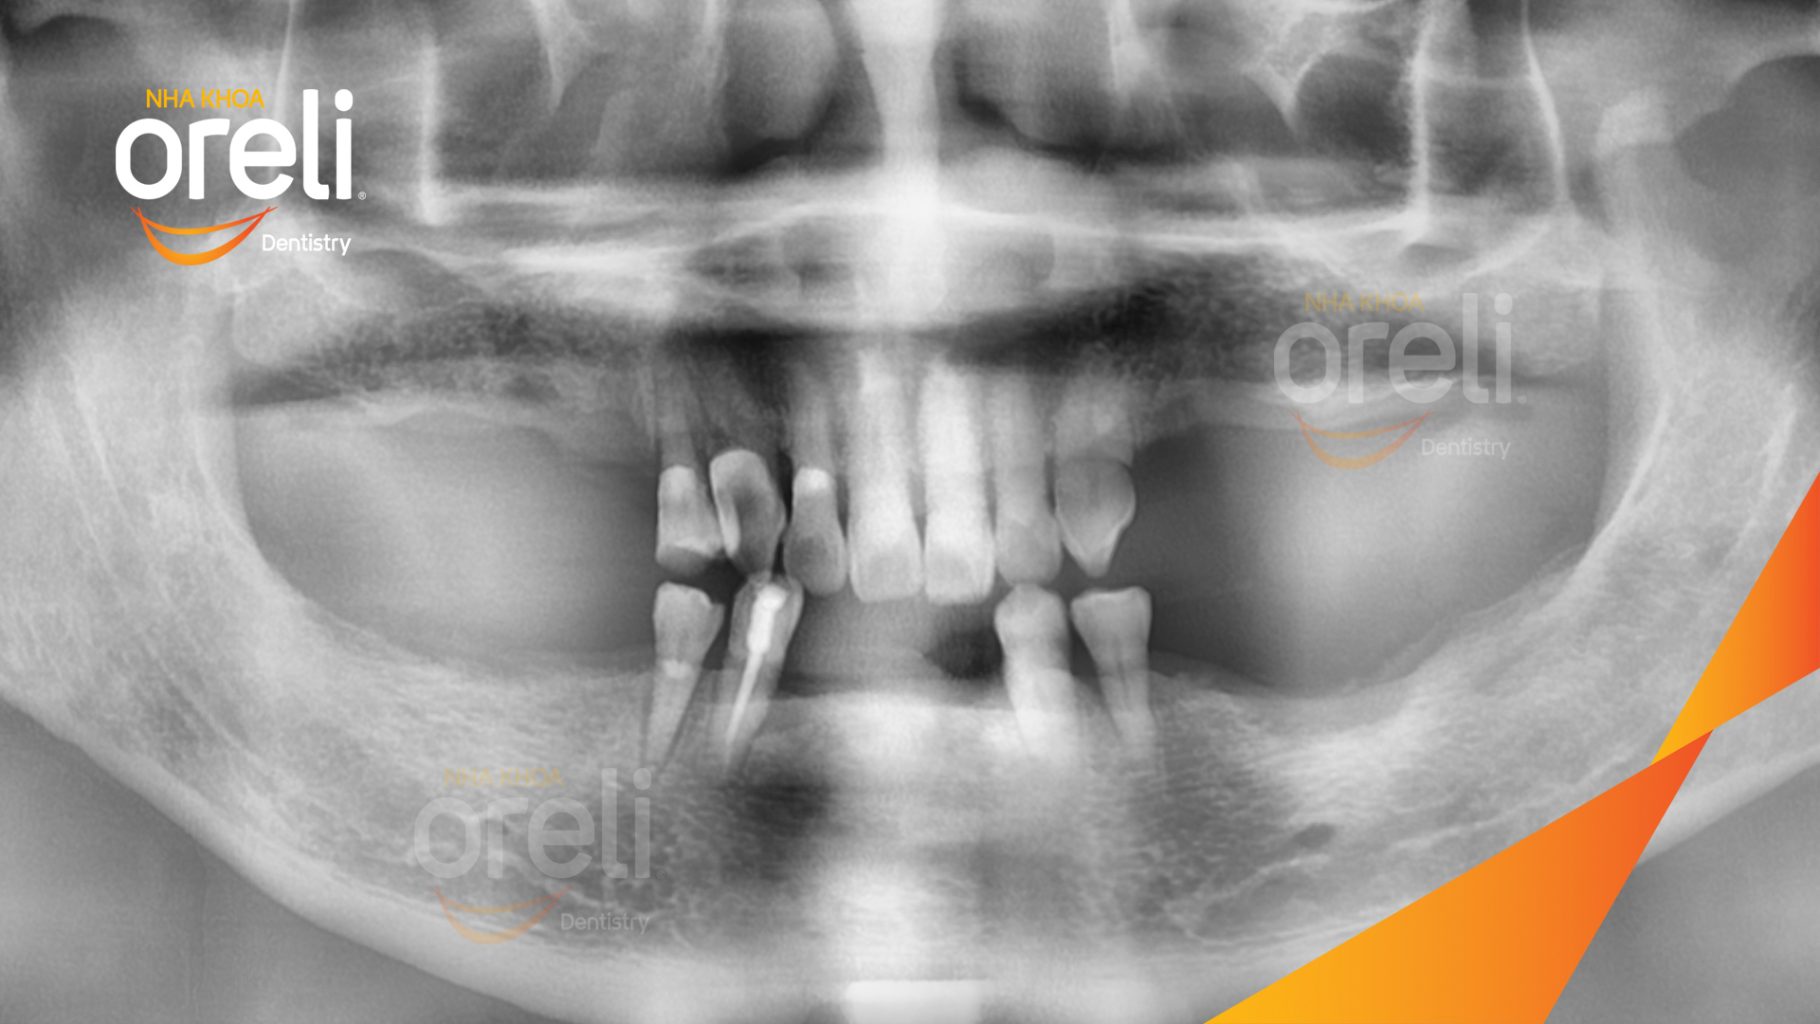

Tình trạng: Mất răng nhai vùng hàm trên và dưới

Hình ảnh thực tế